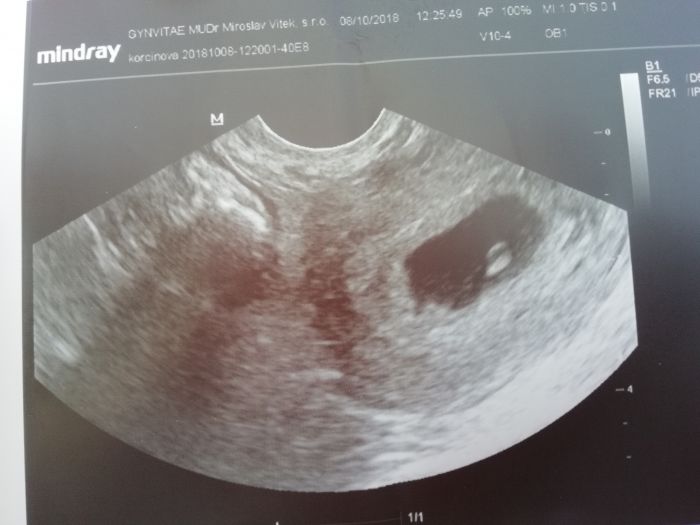

Ahoj holky, já byla na UTZ minule pondělí jako samoplatce. Nemohla jsem to vydržet

Bylo už vidět srdíčko a malý pludek a to jsem byla 6+0tt. Objednaná jsem až na 30.10. a to budu 9+1tt. A jak se cítíte?

A už mate u nějaké foto z UTZ?

Ahoj holky, tak my už máme první fotečku

podle menstruace bychom měli být 8tt a TP kolem 10.června, ale prcek je ještě malinký, takže podle něj to ještě nešlo změřit.